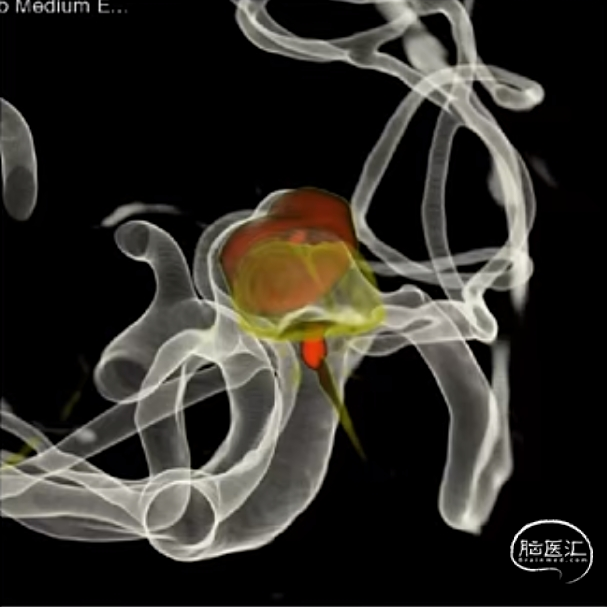

经测量可得动脉瘤宽度平均值为7.0mm,动脉瘤高度为5.18mm,选用WEB™ SL 8*4。

WEB™经由VIA™微导管送入动脉瘤瘤腔并完全释放。术后即刻造影显示WEB™尺寸合适,贴壁良好,分支等血流通畅。解脱后再次造影,可见动脉瘤瘤腔内有明显造影剂滞留。

术后3个月随访,WEB™完全栓塞,动脉瘤完全闭塞。